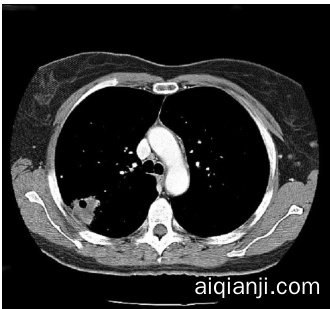

Figure 4: Contrast-enhanced CT scan of the chest for patient #1. A large cavitating lesion was identified in the right upper lobe with pleural involvement and likely extension into the chest wall. In addition, right hilar lymph aden opa thy was suspected. This was the primary malignant lesion in this patient.

图 4: 患者#1的胸部增强CT扫描。右肺上叶发现一个大型空洞性病变,累及胸膜并可能延伸至胸壁。此外,怀疑存在右肺门淋巴结病变。这是该患者的主要恶性病灶。

- Computerized tomography ( CT ) scans of the chest ( Figure 4 ) were obtained. - ( Figure 4 ) and demonstrated a large cavitating lesion in the posterior aspect of the right upper lobe with probable pleural involvement likely representing the primary lesion.

- 进行了胸部计算机断层扫描 (CT) (图 4: )

- (图 4: ) 显示右肺上叶后部有一个大型空洞性病变,可能累及胸膜,很可能代表原发病灶。

User: Where is the lesion located?

Assistant: The lesion is located in the posterior aspect of the right upper lobe of the lung.

User: Is it extending into the chest wall?

Assistant: Yes, the CT scan suggests that the large cavitating lesion in the right upper lobe is likely extending into the chest wall.

User: Can you explain more about the cavitating lesion?

Assistant: Certainly. A cavitating lesion refers to an abnormal mass or growth within the lung tissue that has a cavity or hollow space inside it. This cavity can be formed due to the necrosis (death) of the tissue inside the lesion, leading to the breakdown and disintegration of the affected tissue. Cavitating lesions can be caused by various factors, such as infections (like tuberculosis or fungal infections), autoimmune diseases, or malignancies (cancer). In the context of the CT scan provided, the large cavitating lesion in the right upper lobe of the lung is suggestive of a malignant (cancerous) growth. The cavity within the lesion may be a result of the rapid and uncontrolled growth of cancer cells, which can lead to the destruction of surrounding healthy tissue. It’s important to note that further diagnostic tests, such as a biopsy, would be required to confirm the malignancy and determine the specific type of cancer involved.